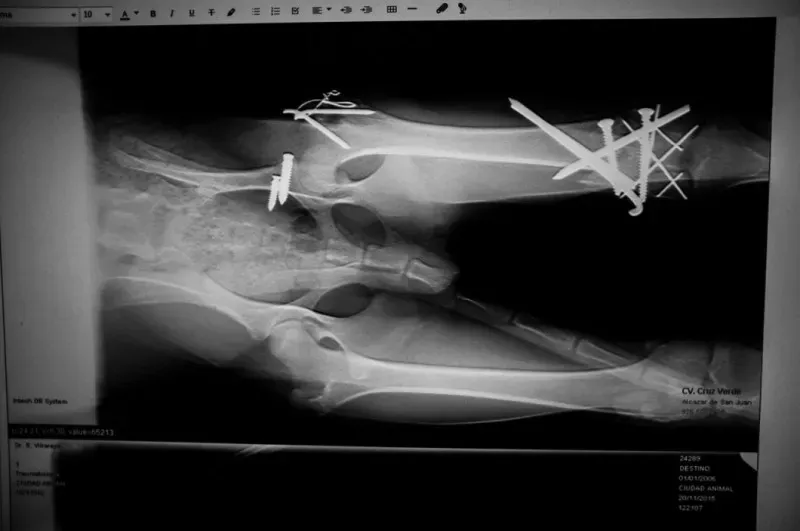

Cicatrices (cicatrici) è un documentario fotografico di David Arribas González realizzato con l’intento di testimoniare il terribile destino a cui vanno incontro, ogni anno in Spagna, decine di migliaia di galgo.

Al termine della stagione di caccia, nel mese di febbraio, i cani che non sono utili, sia per infortunio che per mancanza di competitività o per età, vengono abbandonati o, nel peggiore dei casi, vengono eliminati usando pratiche altamente aggressive come l’impiccagione.

I rifugi per cani e le case di accoglienza cercano di dare una vita dignitosa al maggior numero possibile di questi galgo abbandonati, sperimentando purtroppo condizioni di sovrappopolazione.

A parlare, a questo punto, sono le toccanti immagini realizzate da Arribas.